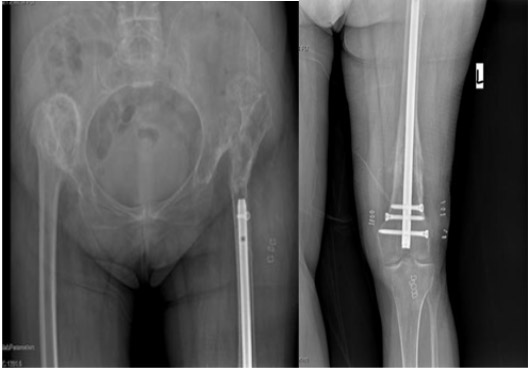

Post-surgery: A nail placement is visible in the left femur.